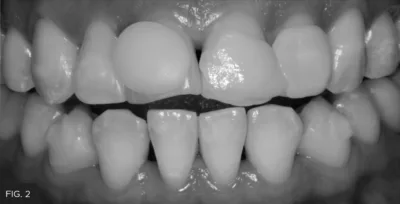

I approached this case, as I do every case, with the Kois 10-step Management Considerations. In this instance, Step 1 (upper anterior), Step 2 (upper posterior), Step 3 (lower anterior) and Step 4 (lower posterior) were applicable. In addition to the fractured teeth, her anterior teeth were misaligned. (FIG. 1A and 1B) The patient agreed to a treatment plan that included an aligner therapy to straighten the four maxillary anterior teeth (lateral incisor to lateral incisor), whiten her dentition, and restore teeth #8 and #9 with composite resin.

A young patient presented seeking restorations for her maxillary incisors. Years of pen chewing had resulted in fractures and incisal wear of teeth #8 and #9. Malalignment of the anterior teeth and arch discrepancies would also require consideration as part of an esthetic solution.